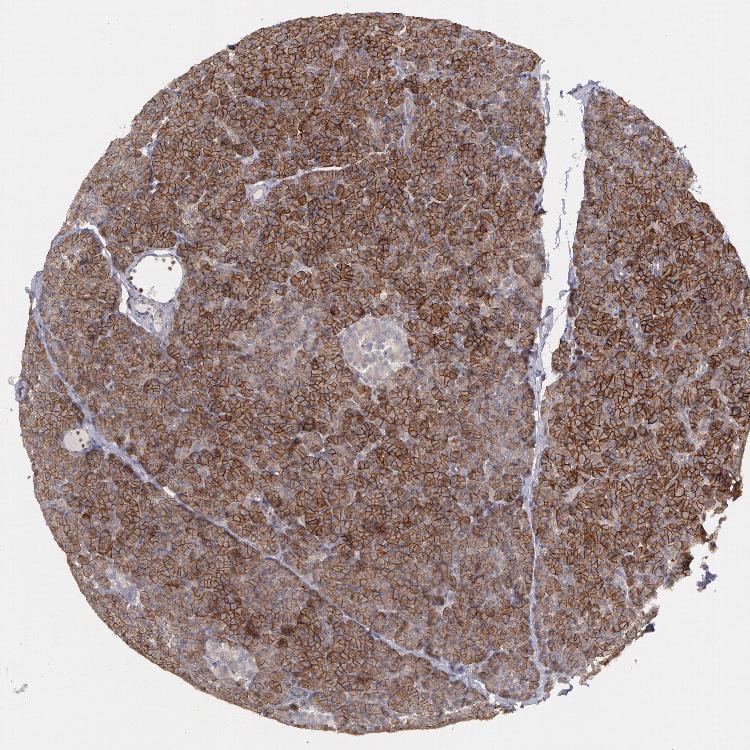

PANCREAS - Antibody stainingi

Antibody staining in the annotated cell types in the current human tissue is reported as not detected, low, medium, or high, based on conventional immunohistochemistry profiling in selected tissues. This score is based on the combination of the staining intensity and fraction of stained cells.

Each image is clickable and will lead to virtual microscopy that enables deeper exploration of all samples and also displays staining intensity scores, fraction scores and subcellular localization as well as patient and tissue information for each sample.

Antibody HPA001383Antibody CAB000043Antibody CAB020416Antibody CAB062555

Exocrine glandular cells MediumNot detectedNot detectedNot detected

Pancreatic endocrine cells LowNot detectedNot detectedNot detected